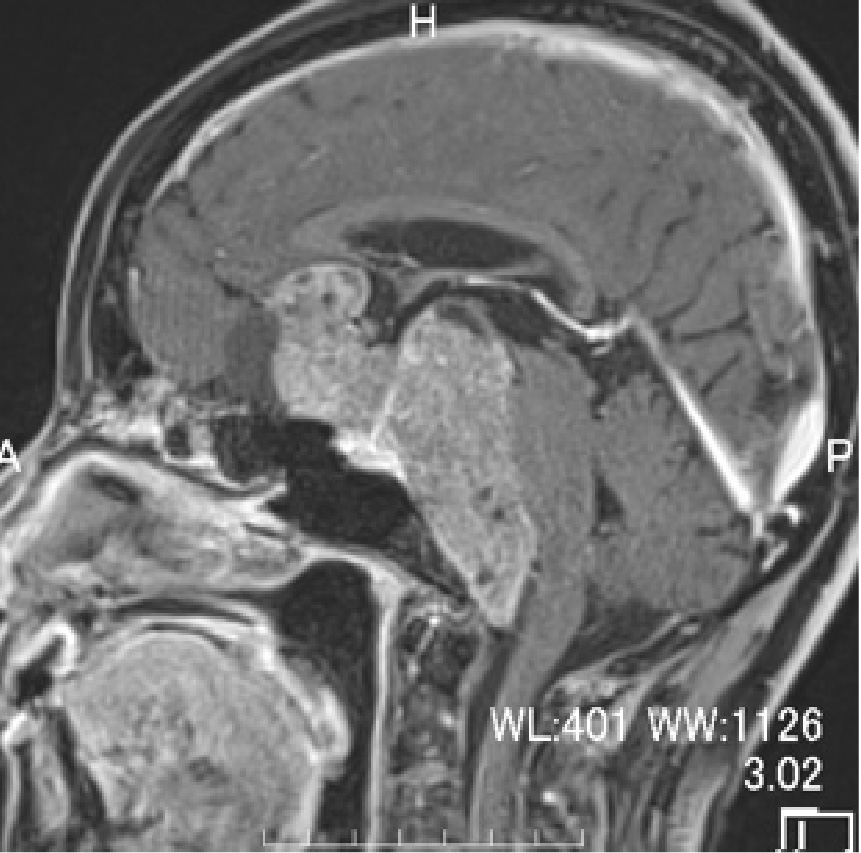

外視鏡と内視鏡を組み合わせて治療した腫瘍のMRI画像です。

髄膜腫:小脳、脳幹、聴神経などが圧迫されている

術前MRI

術後MRI